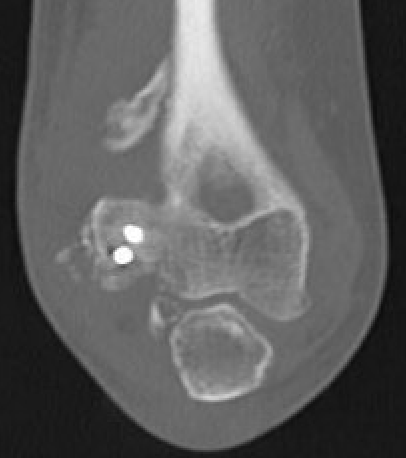

CT

Define anatomical location of the HO prior to surgical excision

Elbow CT Posterior HOElbow CT HO Anterior

cap hocap ho

Zhang et al JSES 2024

- 56 elbows with post fracture HO

- 3D dimensional CT scans

- medial capsule 93%, lateral capsule 80%

- medial supracondylar 57%

- lateral supracondylar, radial head ulnar region 50%